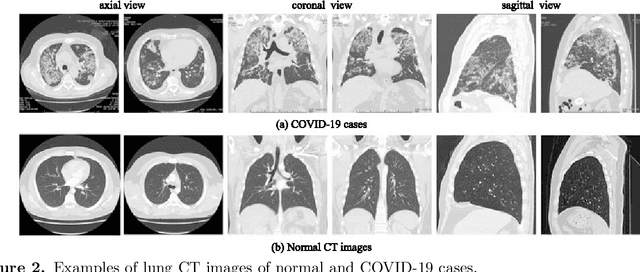

Abstract:The COVID-19 pandemic caused by the SARS-CoV-2 virus has spread rapidly worldwide, leading to a global outbreak. Most governments, enterprises, and scientific research institutions are participating in the COVID-19 struggle to curb the spread of the pandemic. As a powerful tool against COVID-19, artificial intelligence (AI) technologies are widely used in combating this pandemic. In this survey, we investigate the main scope and contributions of AI in combating COVID-19 from the aspects of disease detection and diagnosis, virology and pathogenesis, drug and vaccine development, and epidemic and transmission prediction. In addition, we summarize the available data and resources that can be used for AI-based COVID-19 research. Finally, the main challenges and potential directions of AI in fighting against COVID-19 are discussed. Currently, AI mainly focuses on medical image inspection, genomics, drug development, and transmission prediction, and thus AI still has great potential in this field. This survey presents medical and AI researchers with a comprehensive view of the existing and potential applications of AI technology in combating COVID-19 with the goal of inspiring researches to continue to maximize the advantages of AI and big data to fight COVID-19.